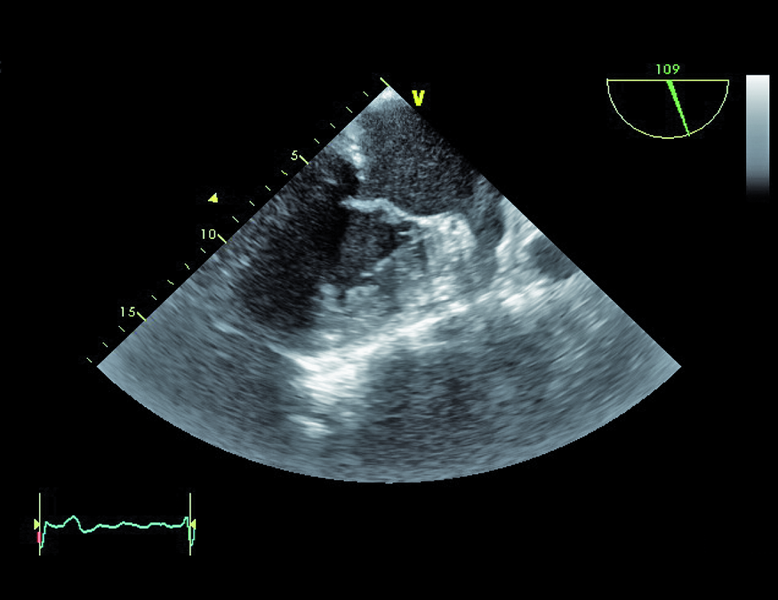

Mężczyzna, lat 79. Jakie patologie można rozpoznać na rycinach?

3. Zwężenie i niedomykalność zastawki aortalnej (ryc. 3).

4. Rozległe zwapnienia płatków i pierścienia zastawki mitralnej (ryc. 4).